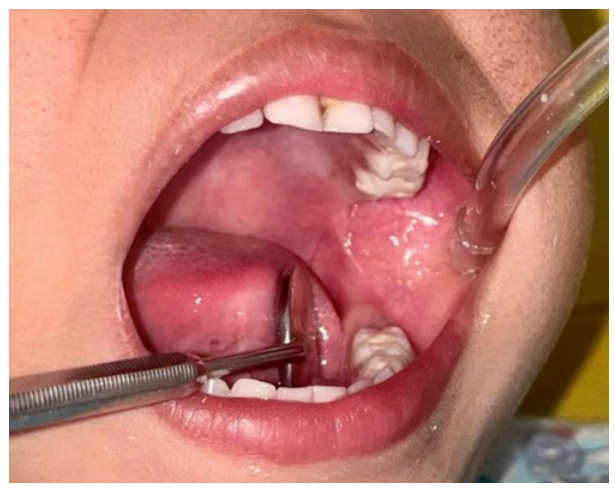

The patient presented to the emergency unit at Trishuli Hospital in the Nuwakot District of Nepal after falling to the ground while brushing. She had stable vital signs and no loss of consciousness. Upon examination, the toothbrush handle was protruding from the left side of her mouth without external skin injury. Intraoral evaluation showed that the brush impaled in the left buccal mucosa and that her primary teeth were intact.

The child’s parents had attempted to remove the toothbrush at home but were unsuccessful. Initial attempts at removal under local anesthesia also failed, prompting surgical intervention under intravenous anesthesia. Approximately 5 cm of the toothbrush, including the head and shank, had penetrated the mucosa.

“A blunt dissection was carried out through the entry wound to the head of the toothbrush, which was then retrieved using soft pulling force,” according to lead report author Santosh Dharel, of the Department of Dentistry at Trishuli Hospital, and colleagues.

The toothbrush pierced the masseter muscle and buccal fat pad but spared the facial artery. Following removal, the wound was irrigated and closed with absorbable sutures. Radiographs were performed to rule out retained fragments or fractures. The patient received antibiotics and analgesics for 5 days and her parents were instructed to provide a soft diet and warm saline rinses.